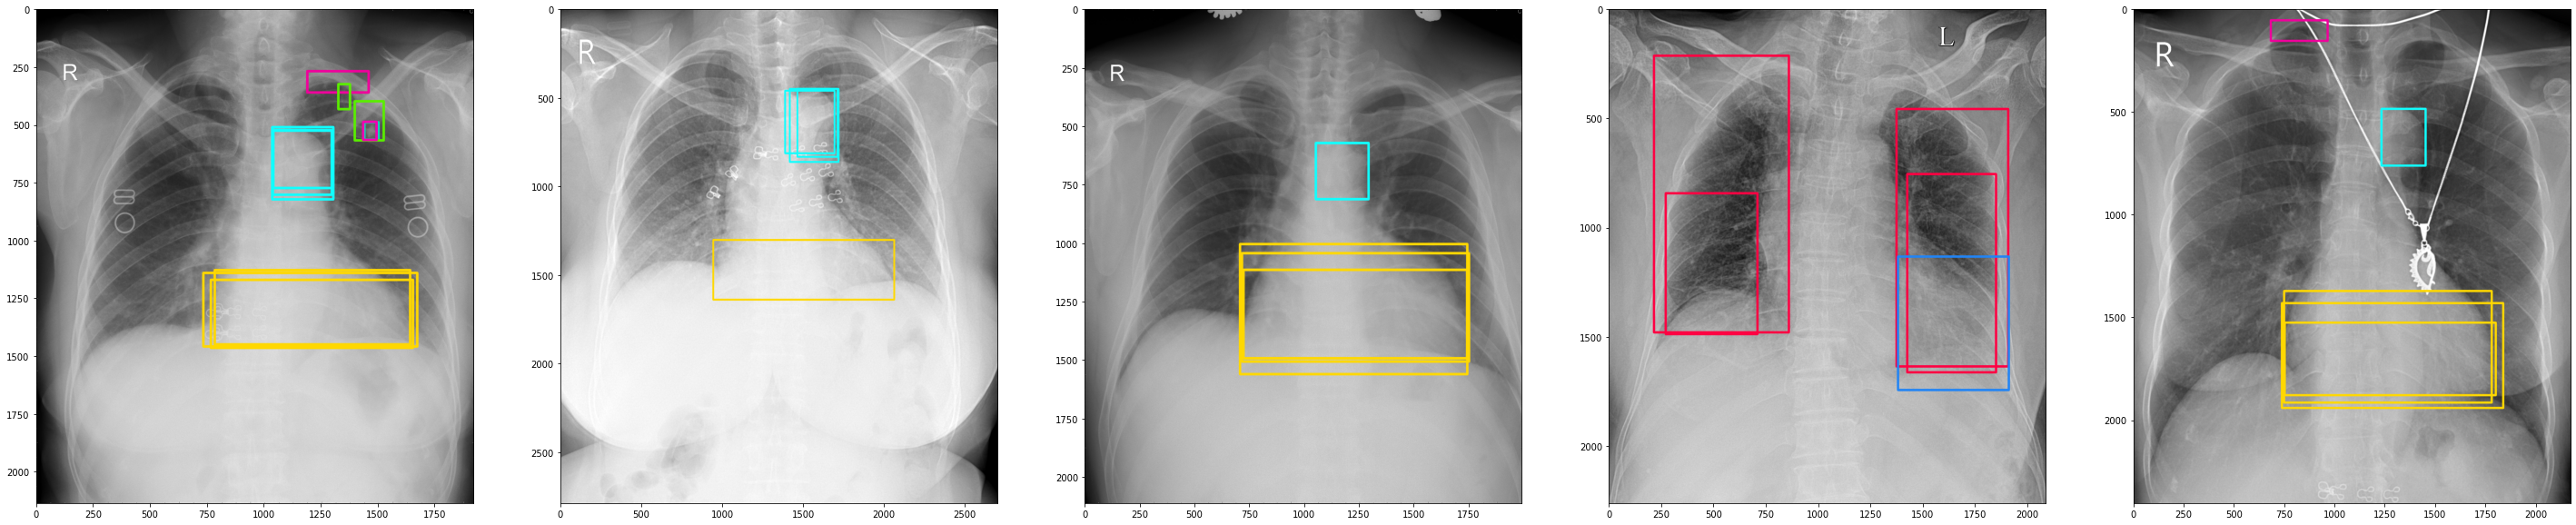

VinDr-CXR [5], by far the largest public chest X-ray database with radiologist-generated annotations. It consists of 18,000 chest X-ray scans that come with both the localization of critical findings and the classification of common thoracic diseases. The dataset includes 15,000 scans for training and 3,000 scans for testing. In particular, the annotations were obtained by a group of 17 radiologists with at least eight years of experience. Each image in the training set was independently labeled by three radiologists, while the annotations in the test set were carefully treated and obtained by the consensus of 5 radiologists. Several examples from the VinDr-CXR dataset are shown in Figure 5.

Refer to caption

(a)

(b)

Figure 5: Visualization of abnormal findings (different bounding box colors represent different findings) from the VinDr-CXR dataset: (top) Each scan in the training set was annotated by three different radiologists; (bottom) Test set annotations were obtained from the consensus of five radiologists.